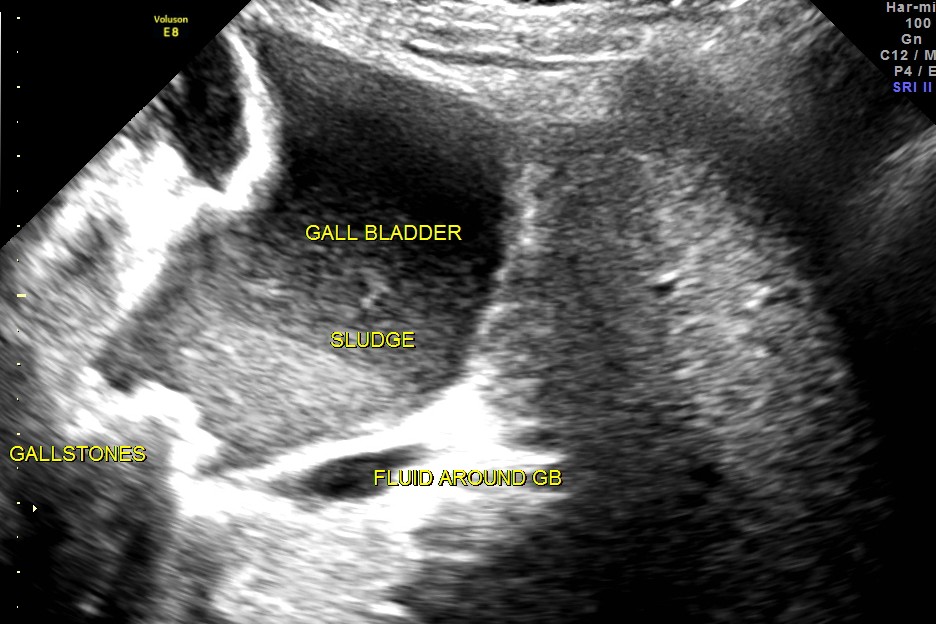

Her ultrasound showed the following findings :

grossly distended gallbladder , with sludge and gallstones and fluid around the gall bladder.

The diagnosis was : acute calculous cholecystitis , cystic duct stones causing a rupture and fluid collection around the GB and loculated sub diaphragmatic collection with reactive mild right pleural effusion . Endometrial fluid collection needed further evaluation.